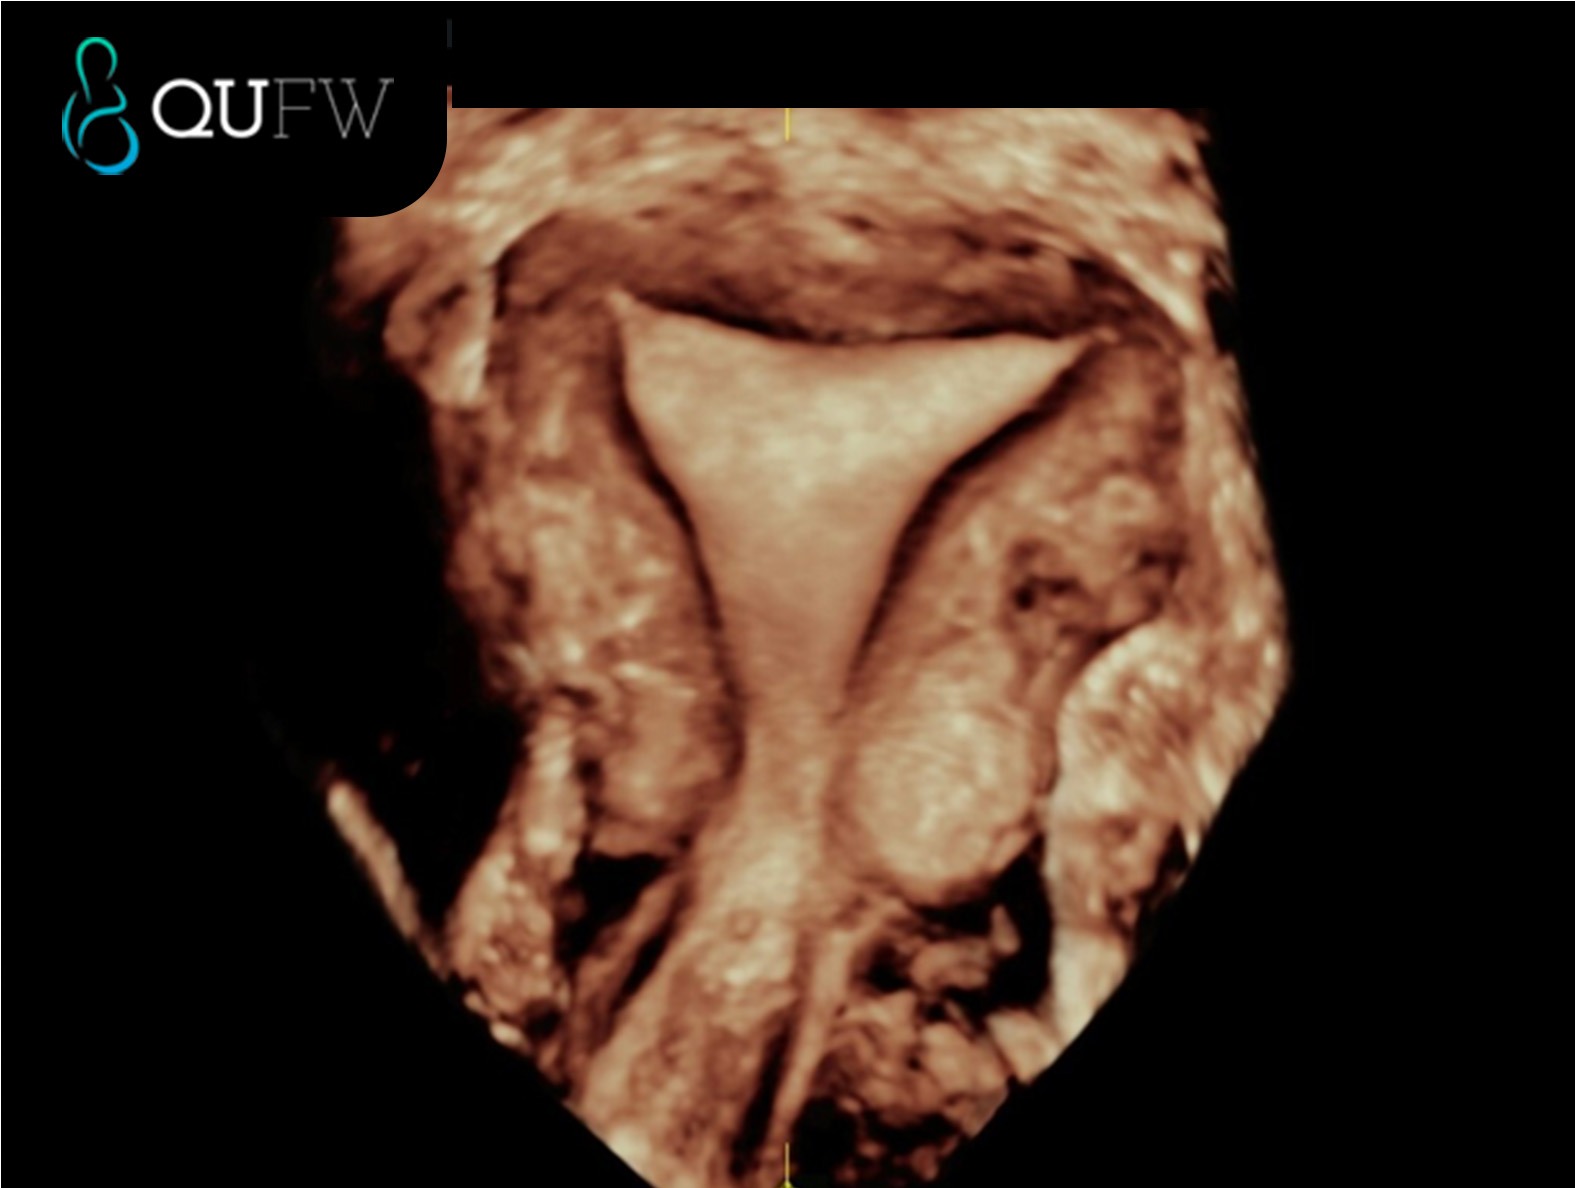

3D reconstructed coronal image of a septate uterus